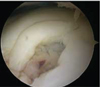

Surgery started with arthroscopy, which revealed an unstable osteochondral defect of . The unstable cartilage remnants were reprocessed with the minced cartilage instrumentation. The underlying avital cancellous bone with cystic changes was completely debrided with a curette and a sharp spoon. An anterolateral miniarthrotomy with a skin incision of 3 cm was performed to insert the cancellous bone, which was harvested from the anterolateral tibial head. Then, the prepared minced cartilage was applicated, and fixation was secured using platelet-rich plasma and fibrin. In this way, the osteochondral defect was completely filled (Figure 2). It was of importance not to overfill the defect, thereby creating a prominent surface. The stratum synoviale of the joint capsule was closed using PDS suture, and the stratum fibrosum was closed using vicryl. Then, the skin incision was closed.

(a)